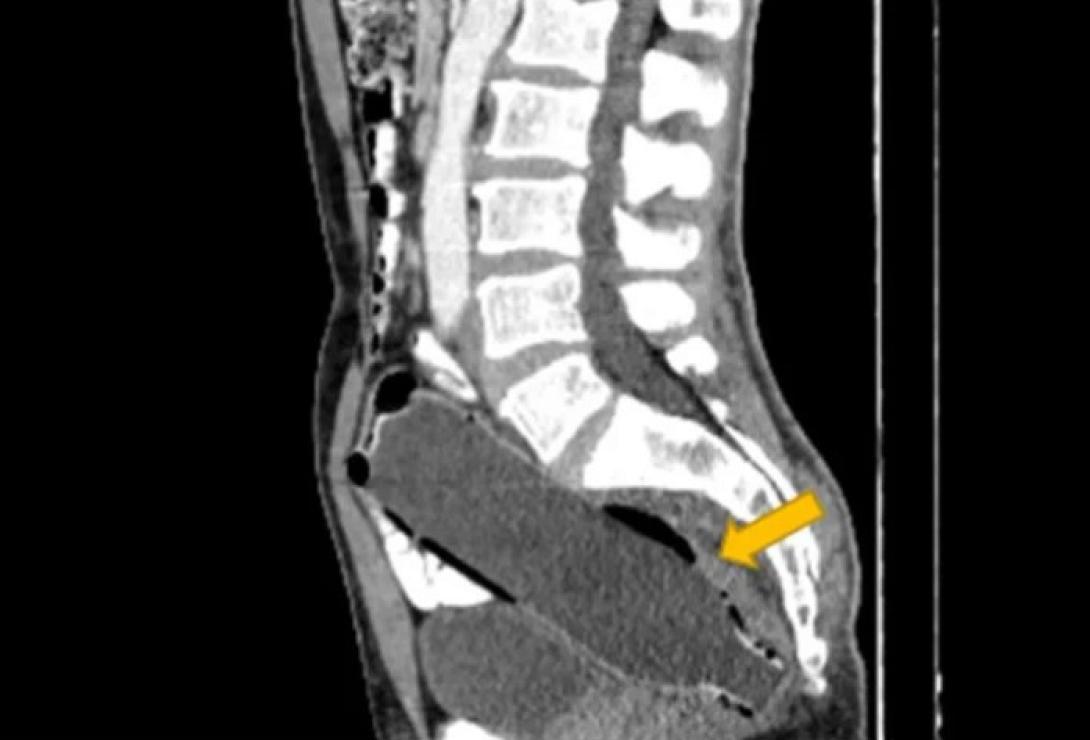

Ένας παντρεμένος άνδρας από το Ιράν αναρρώνει αφού οι γιατροί αφαίρεσαν ένα μπουκάλι νερό από το ορθό του. Το αντικείμενο ανακαλύφθηκε αφού ο 50χρονος έφτασε στο νοσοκομείο με τη σύζυγό του, η οποία ανησύχησε μόλις σταμάτησε να τρώει και άρχισε να υποφέρει από κοιλιακούς πόνους και δυσκοιλιότητα.

Ο άνδρας συνέχισε να κρύβει με επιτυχία το οδυνηρό μυστικό του, μέχρι που αποκαλύφθηκε στους γιατρούς μέσω αξονικής τομογραφίας.

Σύμφωνα με ένα άρθρο στο Clinical Case Reports Journal, ο άνδρας απέφυγε να αναφέρει ότι είχε τοποθετήσει το αντικείμενο μόνος του, λόγω «αμηχανίας» και «φόβου για τη γυναίκα του».

Όταν όμως ήρθε η ώρα να γίνει αυτό, το αντικείμενο παγιδεύτηκε στο παχύ έντερο του άνδρα. Οι γιατροί στο νοσοκομείο Imam Khomeini στο Sari δεν ανέφεραν γιατί ακριβώς το μπουκάλι κόλλησε εκεί, αλλά είπαν ότι η σεξουαλική ικανοποίηση κρύβεται συνήθως πίσω από τέτοιου είδους καταστάσεις. Ο άνδρας ήταν επίσης γνωστό ότι είχε ιστορικό κατάθλιψης, σύμφωνα με το Clinical Case Reports.

Η μελέτη αναφέρει ότι είχε εισαγάγει το μπουκάλι με το κάτω μέρος να μπαίνει πρώτο, προκειμένου να χρησιμοποιήσει το επάνω μέρος ως λαβή για να το τραβήξει έξω.